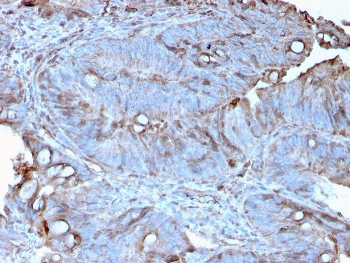

IHC staining of FFPE human colon carcinoma with MerTK antibody (clone TPKR-1). HIER: boil tissue sections in pH9 10mM Tris with 1mM EDTA for 10-20 min and allow to cool before testing.